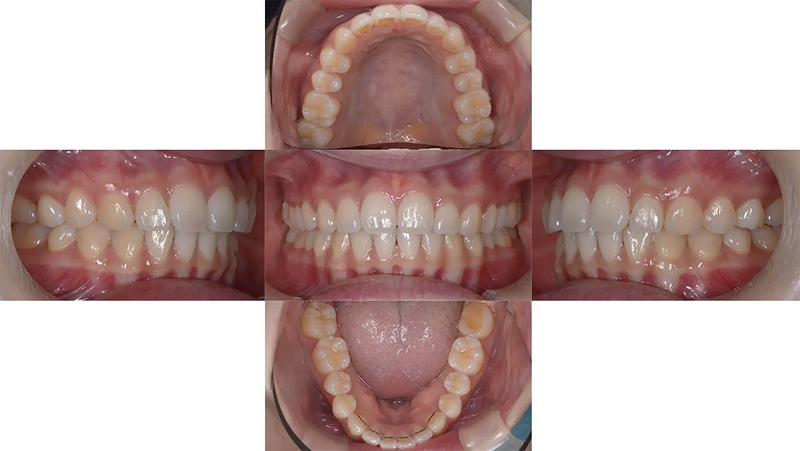

Case02前歯の凸凹を改善した症例

結婚式前に前歯の凸凹を治したいといらっしゃいました。叢生は軽度でタイムリミットは8か月でした。診査の結果、非抜歯なら十分に間に合うと診断しました。上下顎ともに少し側方拡大を行い、歯を並べました。2年後、問題なく経過しています。

ファイナル 2017.10.27

治療2年後 2019.10.12

| 主訴 | 前歯の凸凹が気になる |

|---|---|

| 診断 | 両側アングル1級叢生 |

| 矯正方法 | オーバーレイアーチを併用したマルチブラケット |

| 矯正期間 | 7か月・9回 |

| 費用 | 690,000円(税別) |

| 調整料 | 月1回 5,000円(税別) |